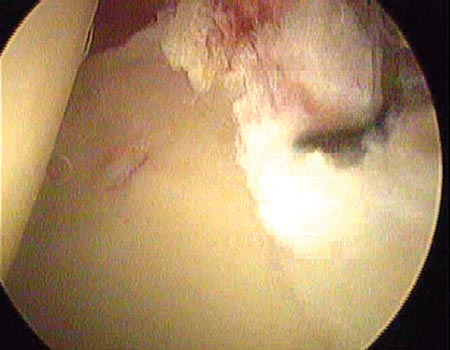

Dentro de las clasificaciones que toman en cuenta la morfología de la lesión mencionamos la enunciada por Lage,18 útil por ser artroscópica, que las divide en (fig. 2, Fig. 3):

Figura 2: Ruptura fibrilar del labrum.

Figura 3: Ruptura longitudinal del labrum.